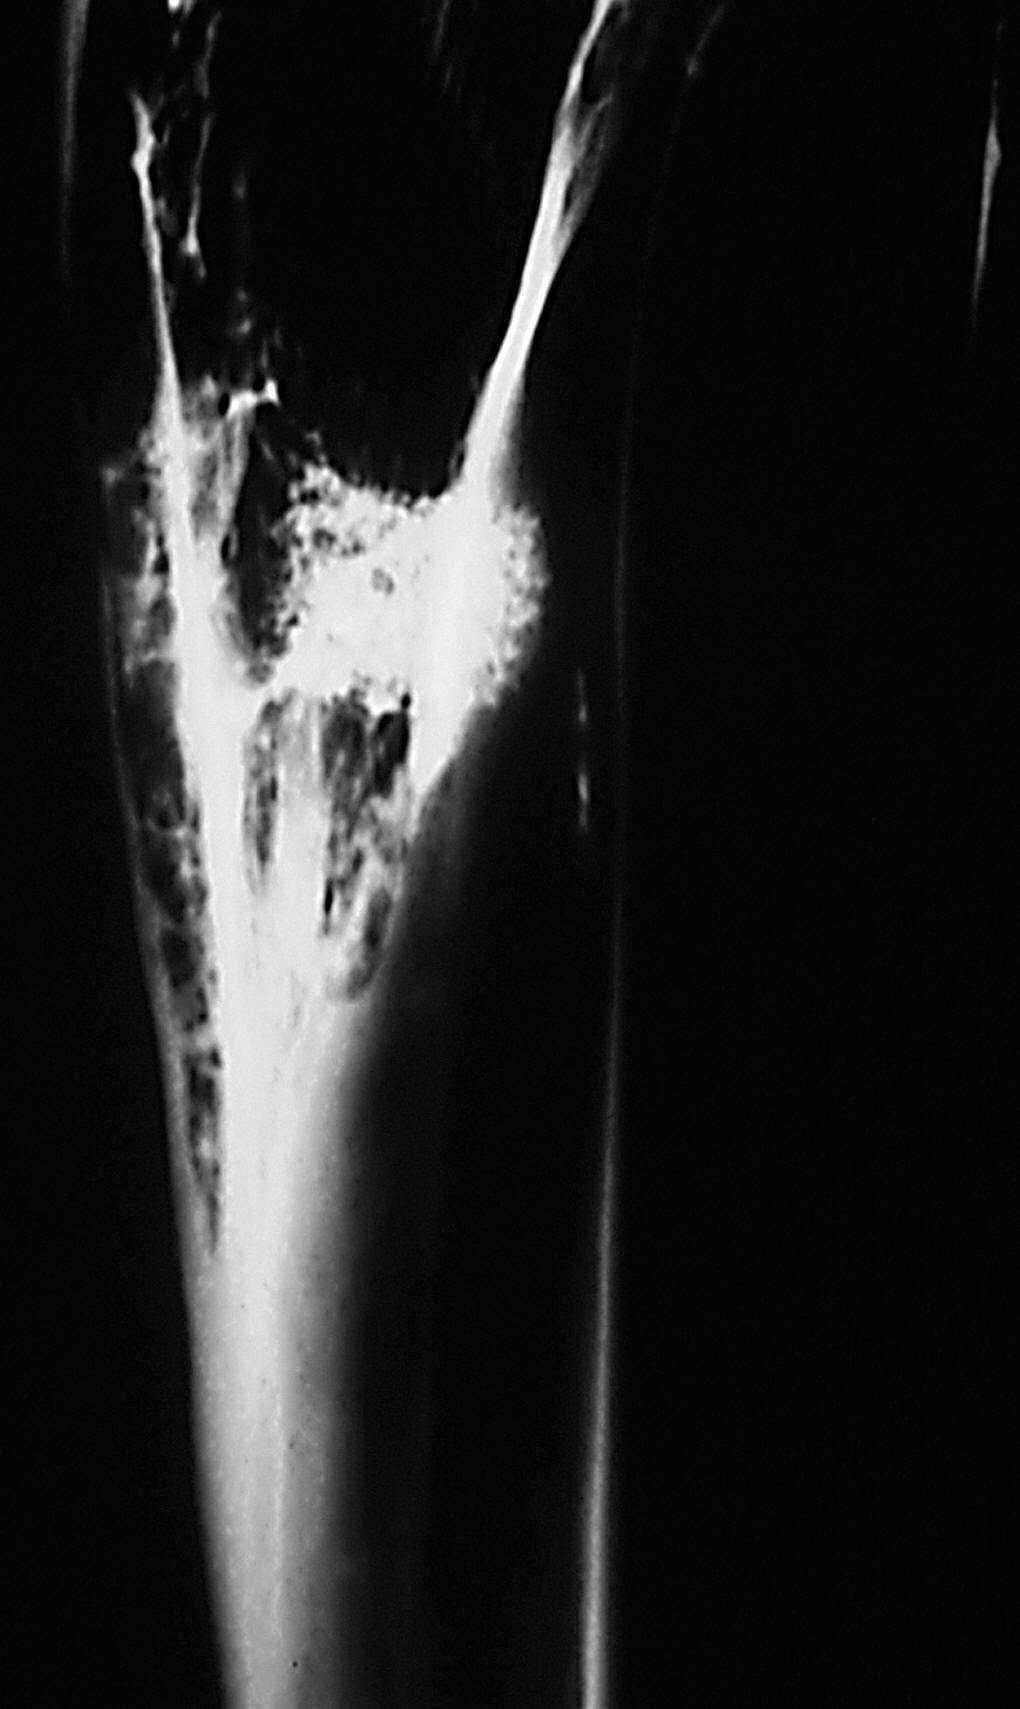

Estudio radiológico. La cortical externa presenta una densidad ósea igual a la cortical adyacente, siendo difícil reconocer el orificio de entrada. El implante junto a la cortical presentó una disminución de la densidad con respecto al grupo anterior, y una forma más ovalada con disminución de la densidad de calcio en su interior. No presenta límites radiológicamente bien definidos.

En algunas zonas existe una continuidad de la cortical con el material implantado, debido a imágenes de trabéculas óseas que parecen atravesarla. No se visualizaron límites radiográficos bien definidos (fig. 8).

Figura 8. Radiografía de tibia. Implante con disminución de tamaño y pérdida de su forma cilíndrica inicial. En algunas zonas se observan trabéculas óseas (↑) que parecen atravesar al implante (*).